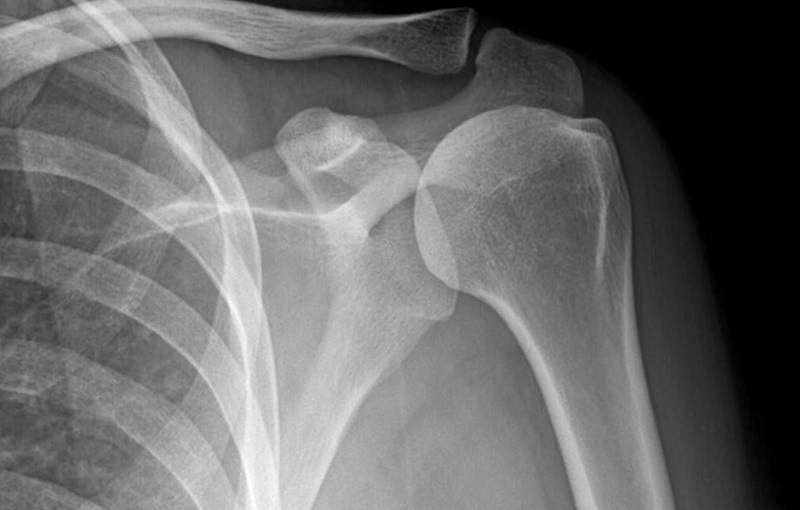

Khi xuất hiện các dấu hiệu nghi ngờ viêm tủy xương, người bệnh cần được thăm khám lâm sàng và thực hiện các danh mục cần thiết theo chỉ định của bác sĩ để kịp thời chẩn đoán và điều trị. Một trong những xét nghiệm hình ảnh đầu tiên thường được chỉ định là chụp X quang. Tuy nhiên, trong vòng 7 – 10 ngày đầu, hình ảnh X quang có thể chưa cho thấy rõ dấu hiệu viêm. Khi chụp lại sau khoảng 12 ngày, những tổn thương viêm xương mới bắt đầu hiện rõ.

Ngoài ra, bác sĩ có thể chỉ định chụp cắt lớp để quan sát chi tiết hơn những thay đổi ở mô mềm do viêm.

Chẩn đoán hình ảnh là phương pháp phổ biến giúp phát hiện viêm xương tủy

Chẩn đoán hình ảnh phát hiện viêm xương tủy nên thực hiện tại cơ sở y tế uy tín